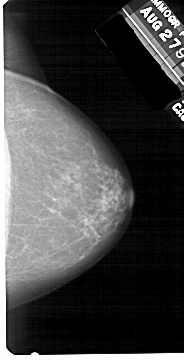

A_1536_1.RIGHT_CC

RIGHT_CC LINES 5386 PIXELS_PER_LINE 2746 BITS_PER_PIXEL 12 RESOLUTION 43.5 NON_OVERLAY